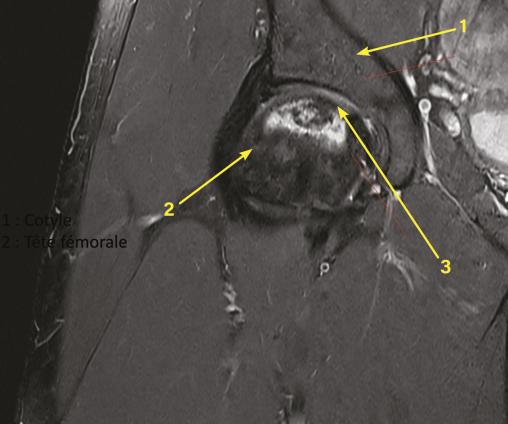

L’IRM retrouve un aspect d’ostéonécrose de la tête fémorale sans déformation de celle-ci.

À l’interrogatoire, le patient ne présente pas de facteur de risque. Son examen clinique n’objective pas de limitation des amplitudes articulaires avec un testing musculaire normal. Il est adressé à un chirurgien orthopédique qui, après un bilan radiologique d’extension, propose une prise en charge par surveillance simple avec risque important de dégradation dans les années à venir, ou chirurgicale conservatrice par forage, greffe avec éviction de l’appui, pour une durée de six semaines. Cette dernière solution est choisie par le patient (fig. 1 ). Le contrôle (IRM) six semaines après l’opération ne montre pas de progression de la maladie, la greffe spongieuse réalisée est toujours présente (fig. 2 ).

À l’interrogatoire, le patient ne présente pas de facteur de risque. Son examen clinique n’objective pas de limitation des amplitudes articulaires avec un testing musculaire normal. Il est adressé à un chirurgien orthopédique qui, après un bilan radiologique d’extension, propose une prise en charge par surveillance simple avec risque important de dégradation dans les années à venir, ou chirurgicale conservatrice par forage, greffe avec éviction de l’appui, pour une durée de six semaines. Cette dernière solution est choisie par le patient (